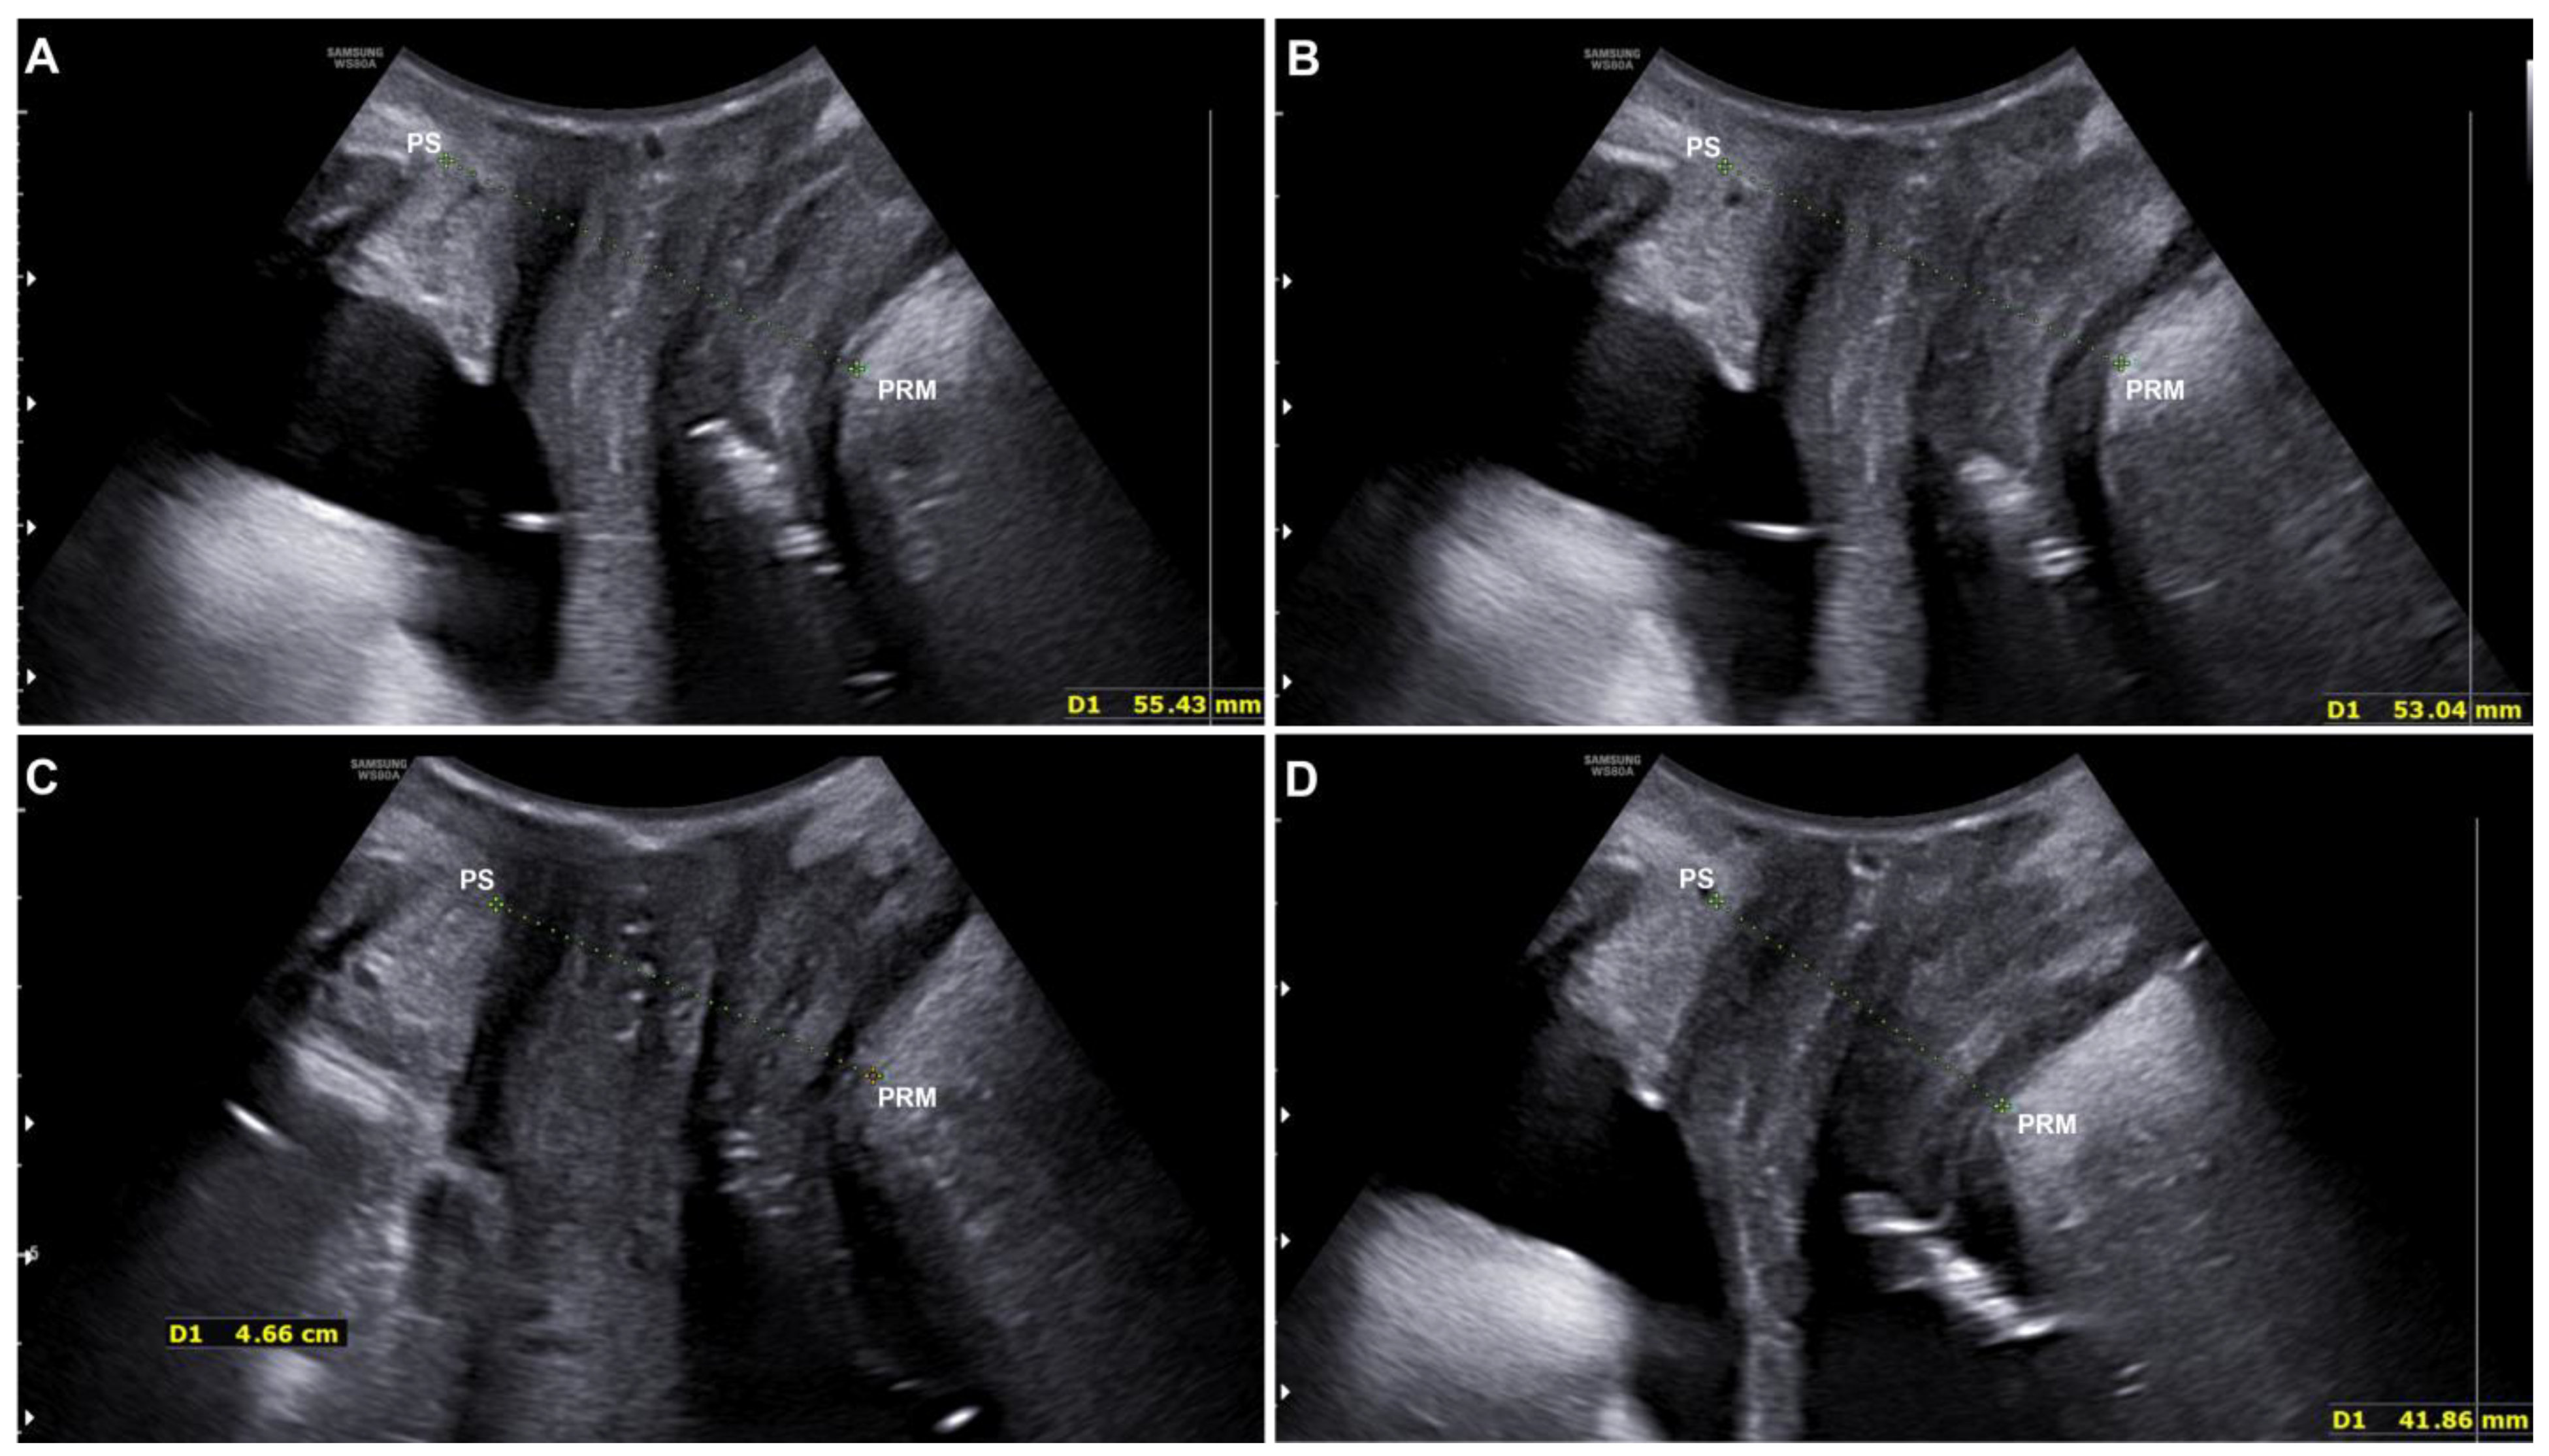

3.2. Quantitative Evaluation with Ultrasound

| At Rest (mm) | Interval Confidence Values | Contraction (mm) | Interval Confidence Values | |

|---|---|---|---|---|

| Before treatment | 56.57 ± 6.52 | 52.72; 60.42 | 47.49 ± 4.86 | 44.62; 50.36 |

| End of the treatment | 54.32 ± 6.38 | 50.55; 58.09 | 44.80 ± 5.07 | 41.81; 47.80 |

| Significance (T0 vs. Tend) | p < 0.001 | p < 0.001 |